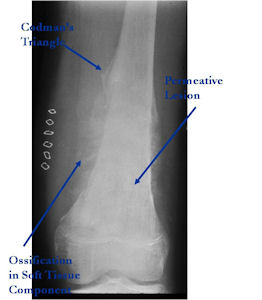

Aggressive Osteoblastoma vs. Osteosarcoma

Osteosarcoma:

- Cellular atypia

- High mitotic rate

- Atypical mitotic figures

- Abundant lacelike osteoid

- Permeative growth into adjacent bone and soft tissue

- Presence of neoplastic cartilage

- No peripheral shell of reactive bone

- Differentiation from osteosarcoma

- Osteoblastomas that are greater than 4 cm and that show prominent periosteal new bone formation may present problems in differentiation from osteosarcoma

- May have foci of lace-like osteoid, high cellularity and more than a few scattered mitotic figures but these characteristics usually occur independently in an osteoblastoma vs all these atypical characteristics being present in an osteosarcoma